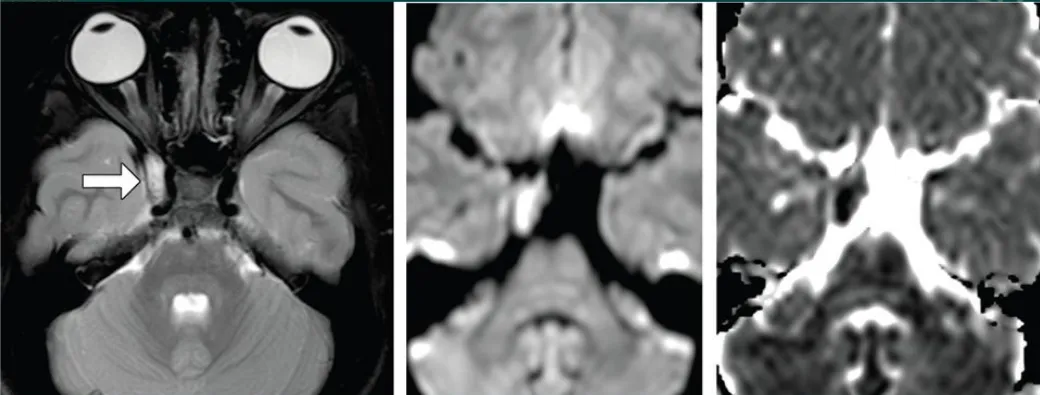

海绵窦血管瘤,T2加权像呈高信号,累及左侧Meckel腔

软骨肉瘤伴岩尖区膨胀性骨质破坏,侵犯左侧海绵窦后部

海绵窦黑色素瘤,需与海绵状血管瘤进行鉴别诊断

图1:T1加权像病灶呈低信号伴周围高信号,T2加权像呈不均匀高信号。增强扫描仅见边缘轻度强化,病变压迫海绵窦内颈动脉。

图2:术后影像显示海绵窦神经血管结构减压良好,无肿瘤残留,FLAIR序列术前高信号完全消失。